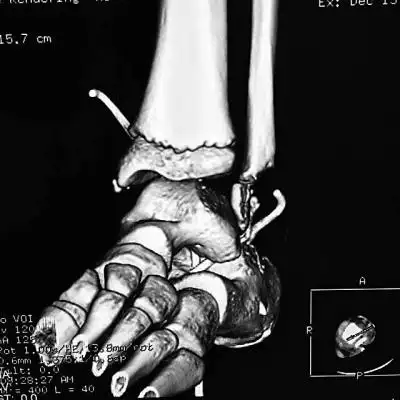

三维ct重建下显示小全脚踝处骨头缺损一大截(画圈处)医院供图

神经性关节病患者的踝关节ct扫描,注意关节面破坏,关节的解体和破碎